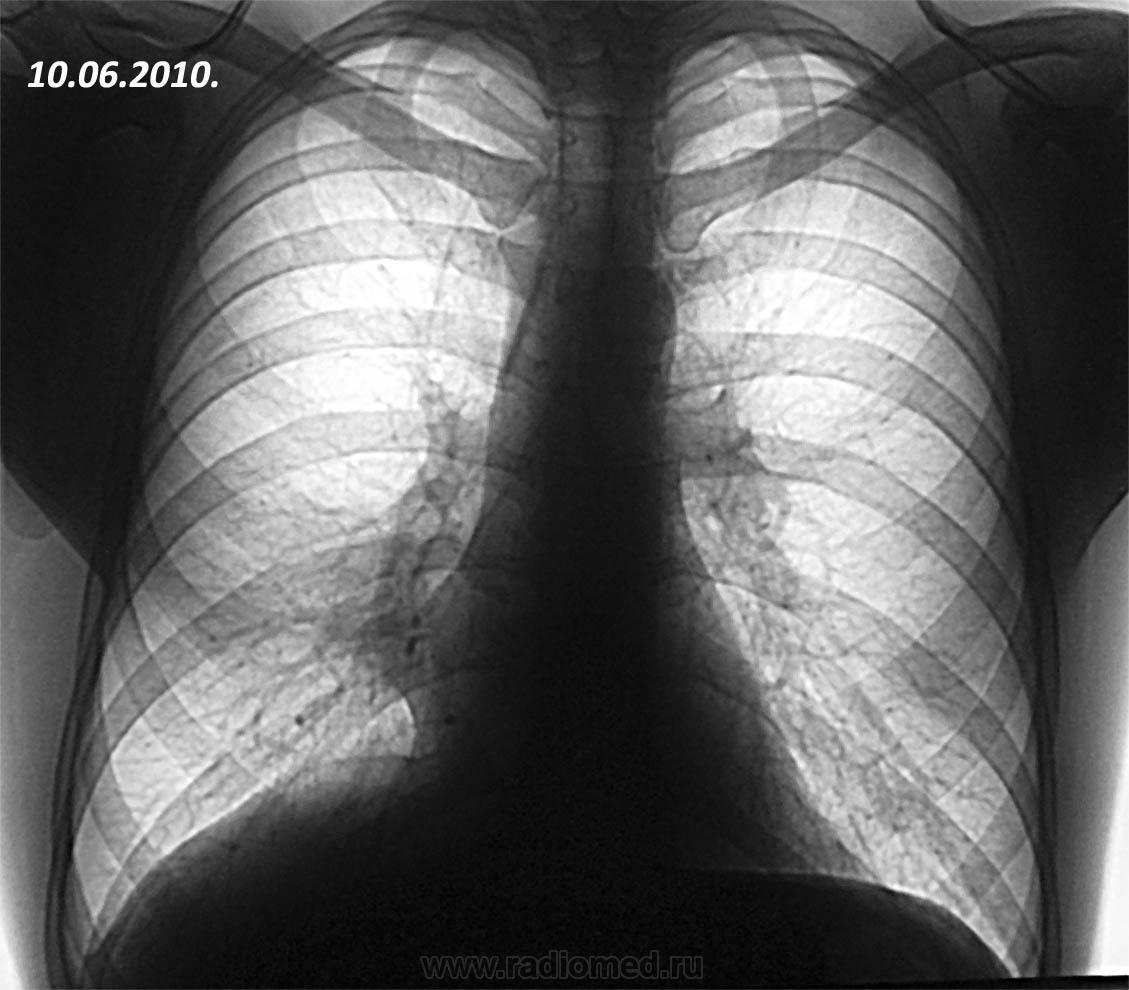

Пациент 1981 г.р., курильщик, жалобы на кашель с периодическими ухудшениями. Беспокоит около полугода. Поступил в пульмонологическое отделение госпиталя в июне 2010 года. Диагноз: плевропневмония. Позже госпитализировался неоднократно. Пневмония сопровождалась ретростарнальным плевритом с элементами организации. Полноценного регресса не было, исход в локальный пневмофиброз. Последнее поступление в ноябре 2011 года. Картина вот такая. В анализах слабый лейкоцитоз. Кашель сухой, мокроты нет.

На ФБС примерно такая вот картинка: 1- плюс-ткань круглой формы, серого цвета, дольчатой структуры, туго-эластичной консистенции при инструментальной пальпации, умеренно кровоточивая при биопсии, неподвижная относительно стенки бронха, 2 - симптом "немого устья" среднедолевого бронха, обтурированного данной опухолью, проходимость за нее только для щипцов, 3 - локальная гиперемия устья с/д бронха справа, 4 - инфильтрация шпоры с/д бронха справа. Цитология - метаплазия эпителия. Гистология еще не готова. Пациент морально простимулирован, в течение 2 дней уехал в Москву в головной госпиталь.

Картина больше похожа на ателектаз средней доли, возможно только 5 сегмента

Нет. Эта ткань не гранулема. Больше на аденому похожа. Ателектаз всей средней доли.

Изначально - не похоже, а на последней ФОГК? как Вы опишете изменения? В протоколе отмечена инфильтрация с втянутой плеврой. Да, классики-ателектаза нет. НО это снимки после 7 дней АБ терапии, в крови лейкоцитоза нет. К тому же на ФБС за опухоль можно пройти только форцептам (диаметр 2.5 мм), видимого просвета СДБ вообще не определялось.

Влез в старые сообщения. У данного пациента после операции - карциноид.3 года ходит довольный, ни разу не болел (тьфу-тьфу).